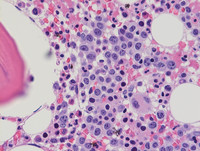

Figure 2: H&E in Paroxysmal Nocturnal Hemoglobinuria

Shown is a bone marrow biopsy from the patient. At low power (left) erythroid hyperplasia is present with a cluster of erythroid precursors (arrow). On higher power (right), the erythroids are left shifted with megaloblastoid features.